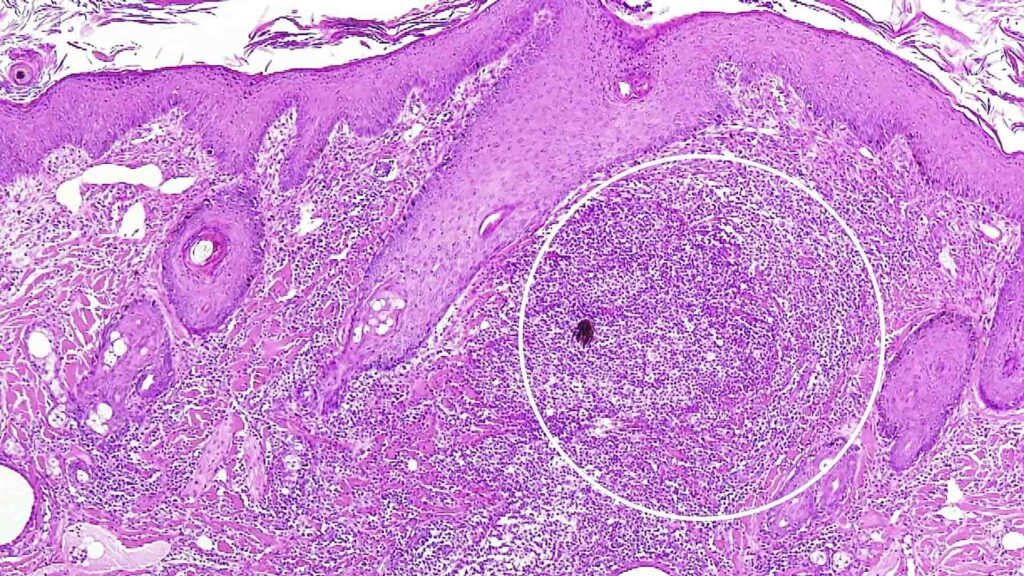

ヨークシャーテリアでは皮膚糸状菌症の典型的な円形脱毛だけでなく、結節性病変として発症するケルスス禿瘡(ケリオン)にも注意が必要です。真皮内で感染毛を中心に好中球・マクロファージが浸潤し、化膿性肉芽腫を形成するため、ウッド灯や表層搔爬では検出困難な場合があります。診断にはトレパンによる皮膚病理検査が有用です。治療はイトラコナゾール5mg/kg SIDを基本とし、真皮病変のため長期投与が前提となります。投薬は食直後とし、肝酵素上昇に留意して定期的な血液検査を実施します。さらに環境中の真菌管理と家族への曝露対策が再感染防止の鍵となります。